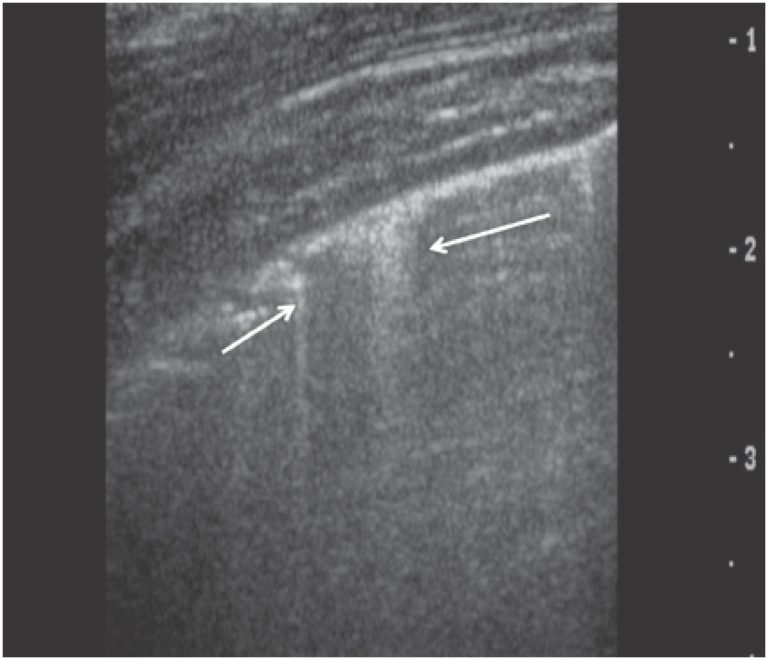

Ultrasound examination of the chest has advanced in recent decades. This imaging modality is currently used to diagnose several pathological conditions and provides qualitative and quantitative information. Acoustic barriers represented by the aerated lungs and the bony framework of the chest generate well-described sonographic artifacts that can be used as diagnostic aids. The normal pleural line and A, B, C, E and Z lines (also known as false B lines) are artifacts with specific characteristics. Lung consolidation and pneumothorax sonographic patterns are also well established. Some scanning protocols have been used in patient management. The Blue, FALLS and C.A.U.S.E. protocols are examples of algorithms using artifact combinations to achieve accurate diagnoses. Combined chest ultrasonography and radiography are often sufficient to diagnose and manage lung and chest wall conditions. Chest ultrasonography is a highly valuable diagnostic tool for radiologists, emergency and intensive care physicians.